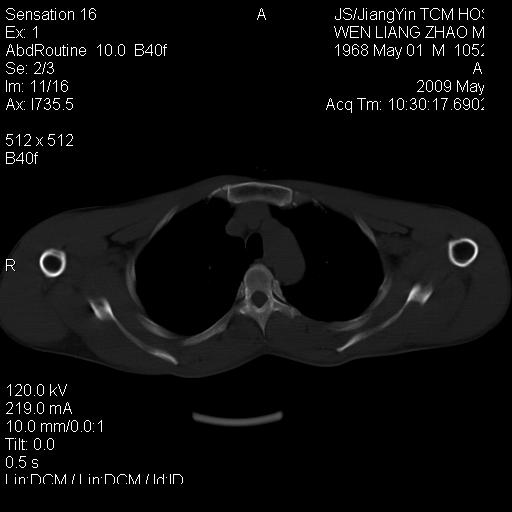

标题: CT19762:左侧喙突处压痛二年。考虑骨样骨瘤。 [打印本页]

标题: CT19762:左侧喙突处压痛二年。考虑骨样骨瘤。

左侧喙突处压痛二年。考虑骨样骨瘤。

病灶外缘膨胀明显,灶缘硬化较少,结合病史较符合骨母细胞瘤,其他亦不排除如软骨及软骨母细胞瘤等(病灶形态,成份较符合,发病部位也符合,只是年龄较大),骨样骨瘤多有较明显的自发性痛,且夜间痛明显,病史为压痛两年,不太符合.

多考虑内生性软骨瘤。年龄及发病部位及病史不支持骨样骨瘤。

支持骨样骨瘤(瘤巢小于1.5mm),骨母细胞瘤又称为巨大骨样骨瘤指瘤巢大于2cm的骨样骨瘤.

首先考虑内生软骨瘤,其次才考虑骨样骨瘤。

良性骨病(低毒感染,成软骨细胞瘤.)